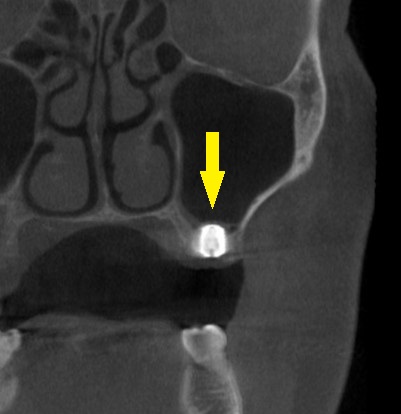

レントゲン、CTを撮影すると、骨幅は十分ですが、高さが3~4mmと、通常のインプラント埋入を行なうには、かなり不足でした。

本日、左第一大臼歯に直径6.0mm長さ7mm、第二大臼歯部位に直径5.0mm長さ7mm、のインプラント埋入術を施行しました。

下の写真が手術前後のCTです。